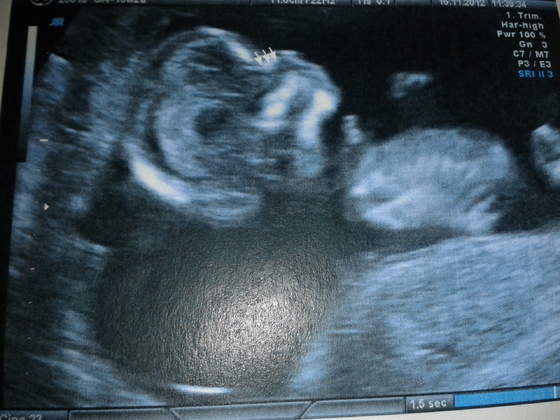

Zdjecie siusiaka bardzo niewyrazne, ale opisalam w paincie:-D N- noga, S - siusiak:-D

Zobacz załącznik 516063

A tu profil z zaznaczona koscia nosowa:-)

Zobacz załącznik 516064